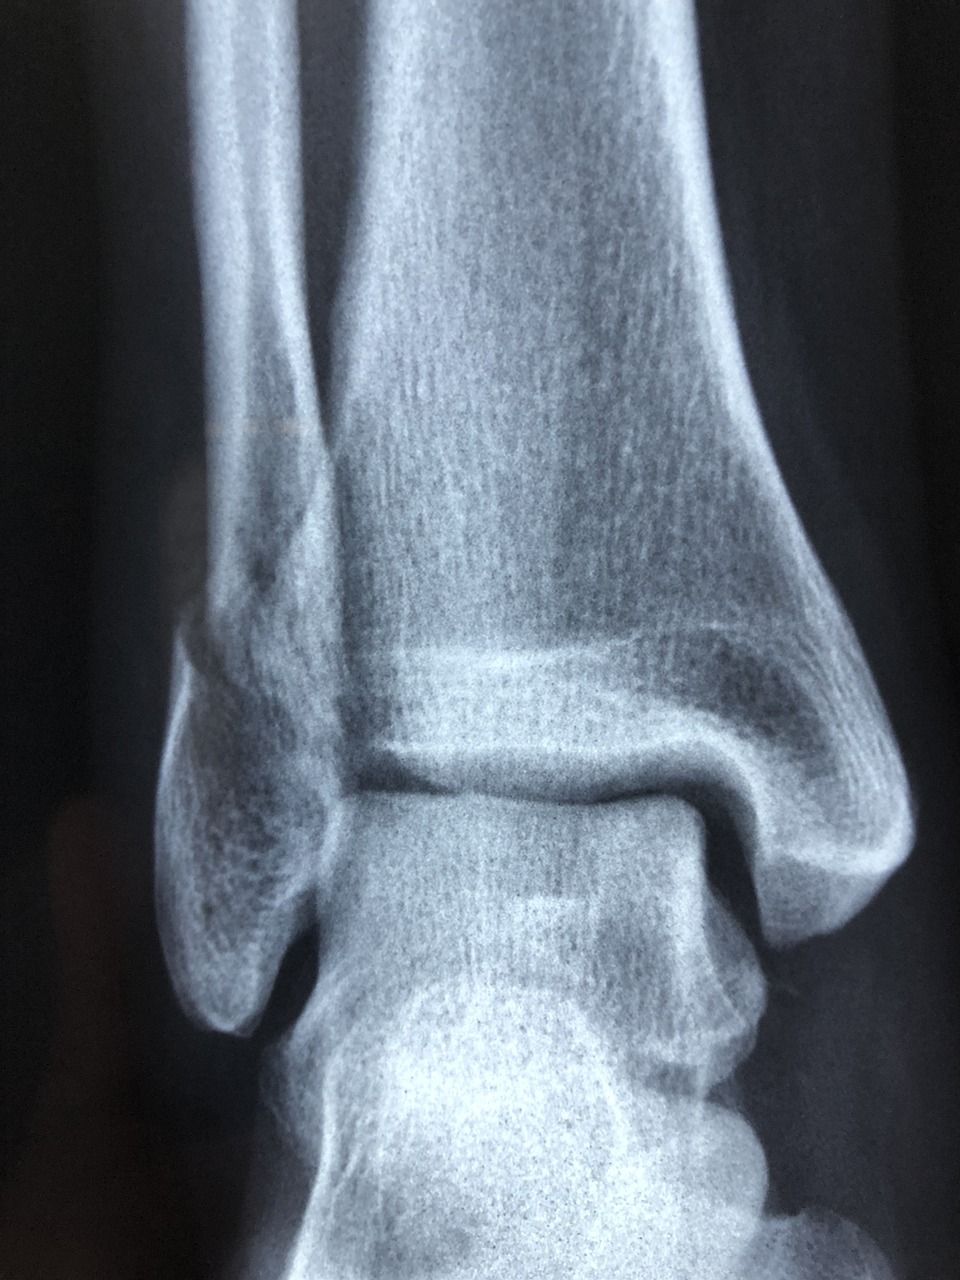

Røntgenundersøgelse

03 oktober 2024